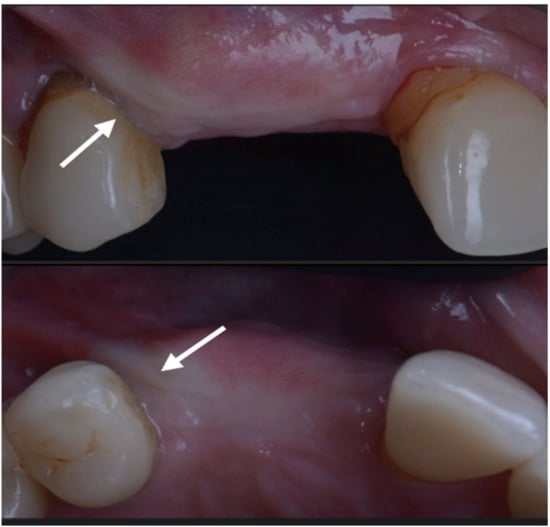

The case has been followed for over three years and the stability of the soft and hard tissue are proof of the GTR effect of GBR. In this case, all parameters were restored in a still very young patient (Figure 12). The important aspect of the GTR effect is that teeth otherwise compromised at a young age are back in function with the support of both soft and hard tissue and all of this with only two surgical procedures. The presence of interdental-implant papilla is important to prevent food impaction and make the maintenance similar to that of the natural dentition. PPD at the time of recall were 2 mm to the distal of 15 and 2 mm to the mesial of 17; compared to the baseline, the gain of attachment was 4 mm for 15 and 5 mm for 17.

Figure 12.

Baseline and clinical and radiographic result 36 months after loading.